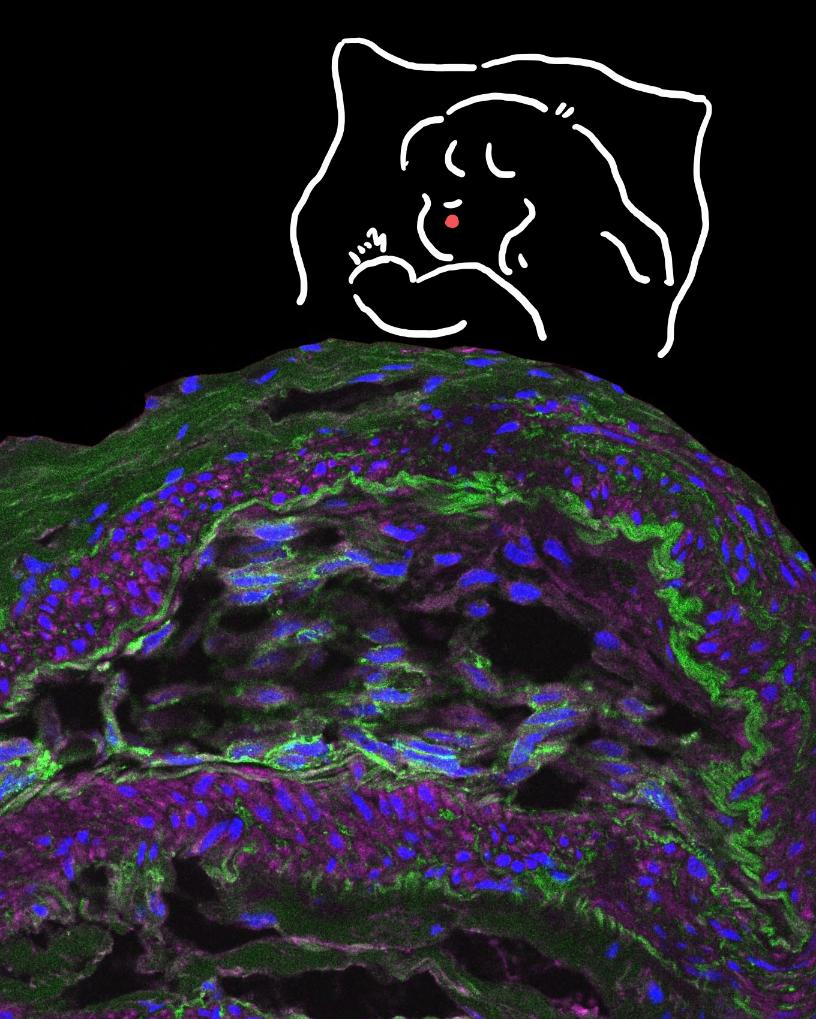

作品《深海寻梦》。新华网发(作者:沈静恬)

作品《深海寻梦》以人卵巢癌组织的免疫荧光染色图像为主画面,通过显微技术与艺术创作的融合,将生命科学的微观世界转化为一片深邃的“海洋”。画面上方手绘的“寻梦者”小女孩,以简笔线条勾勒出对科学之海的无限遐想。